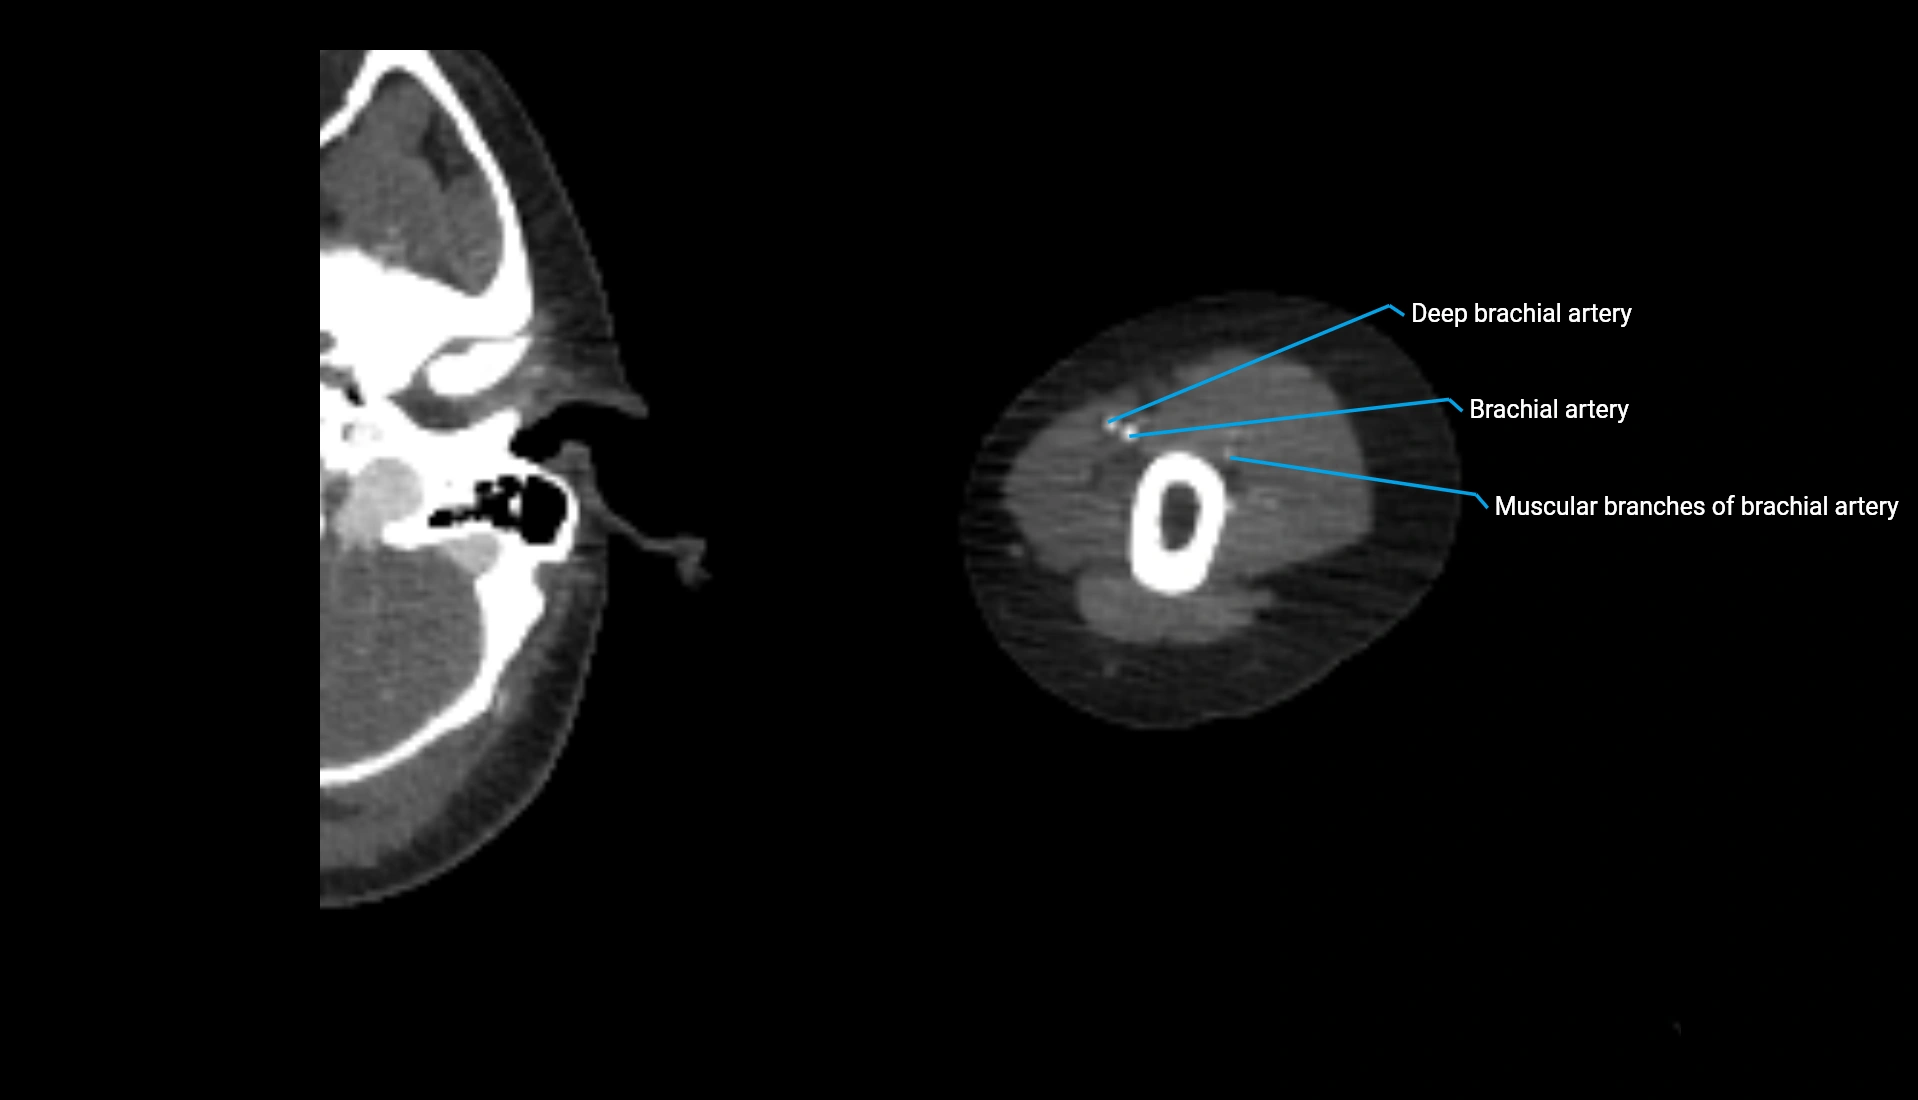

CT Appearance

Non-Contrast CT:

• Cortex: High-density, sharply defined

• Subchondral bone: Dense cancellous matrix

• Articular surface: Smooth concave contour articulating with the capitellum

• Excellent for evaluating bone integrity, alignment, and subtle fractures

Post-Contrast CT:

• Bone: No enhancement

• Joint capsule and synovium: Mild enhancement outlining the joint

• Improves contrast between soft tissues and bony margins

• Useful in detecting subtle joint abnormalities or postoperative changes